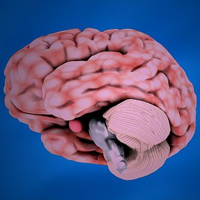

Know Your Anatomy